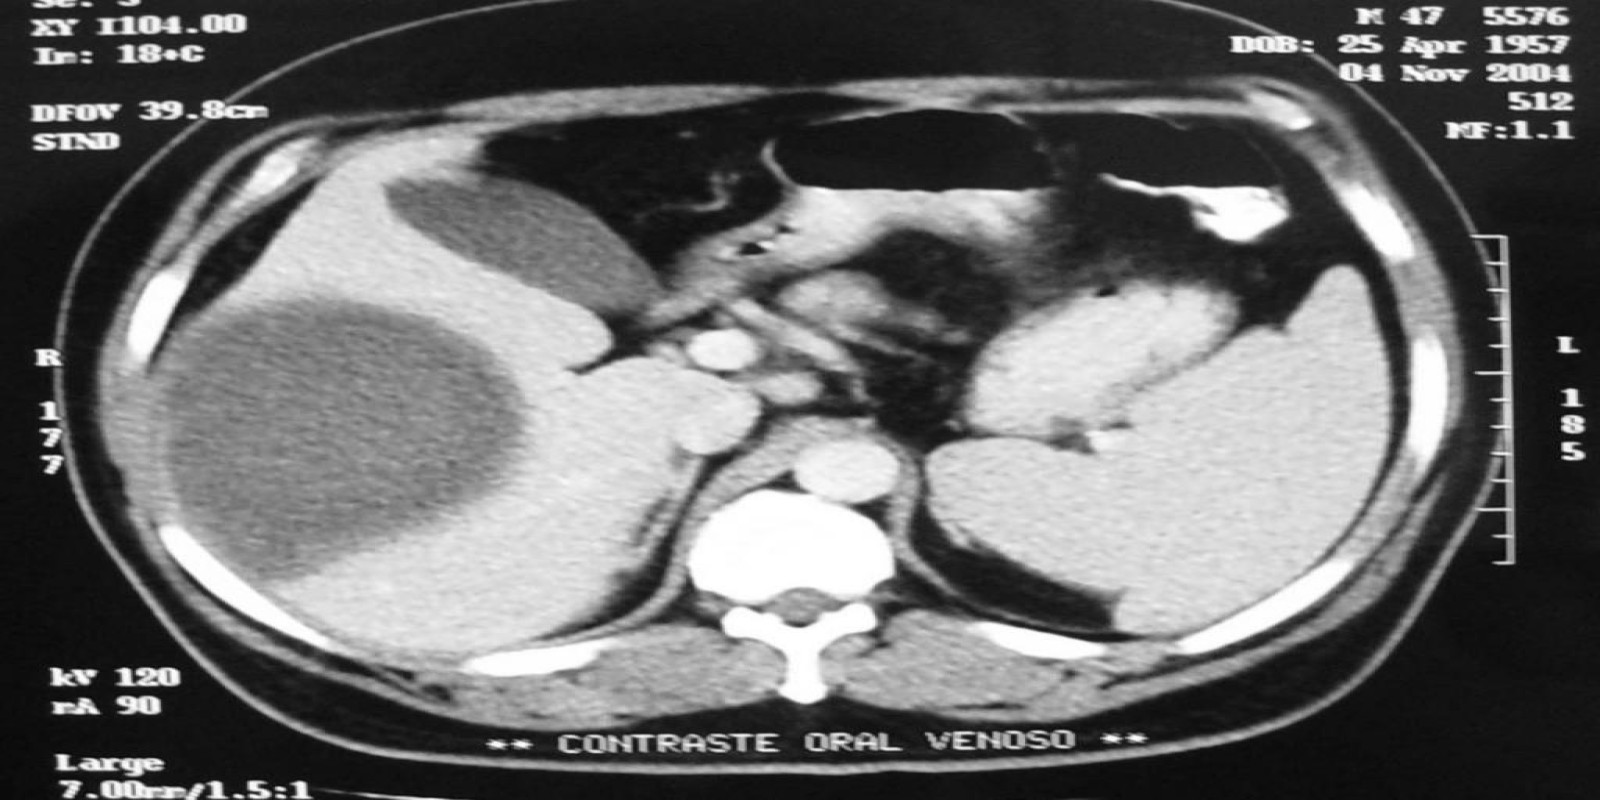

Abscesso Hepático

Liver abscess

Caso Código 042B de Abscesso Hepático

Cod.: 042B